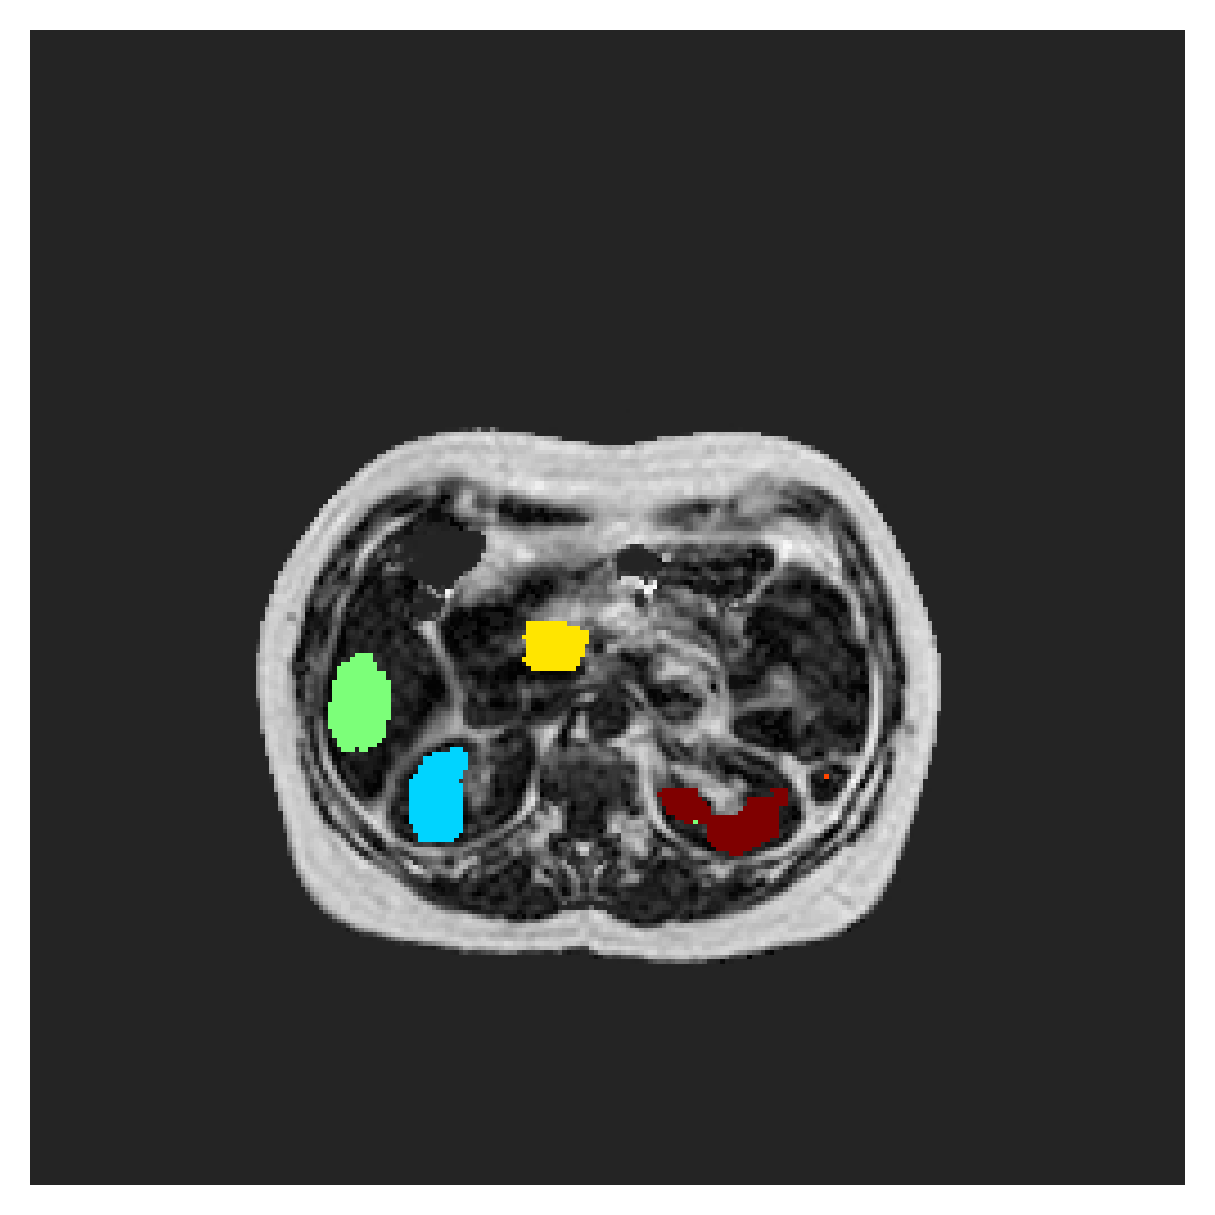

POEM

The Prospective investigation of Obesity, ENergy production and Metabolism (POEM) is a local (not currently publicly available; PI: L. Lind, see [22] for details) cohort of whole-body fat/water separated MR images. Full annotations of the liver, kidneys, bladder, pancreas and spleen are available for 50 subjects, providing a challenging segmentation dataset with heavily imbalanced classes of varying shapes. The resolution of the data is anisotropic, with reconstructed voxel size of in left-right, anterior-posterior and foot-head directions, respectively. For additional technical details regarding the acquisition and specifications of the images see [22].

The images contain two channels, one for water and one for fat content. For training, we normalize the volumes (per channel) and use 2D slices in the coronal plane, sized . The weak annotations are created synthetically, following the same procedure as described for the ACDC dataset.

5.2 Abdominal organ segmentation

In Table 3, the average DSC and HD95 results are shown (both using 2D and 3D distance maps) for the task of abdominal organ segmentation in POEM data (for boxplots see figures 8 and 9). We see that training with and (with distances calculated on 2D slices) performs comparably, while using and produces lower scores in both DSC and HD95 metric. On this dataset, the CRF-loss is able to compete with the boundary loss-based training strategies, even outperforming them on most classes. Most notably, all models trained with boundary loss appear to have a hard time segmenting the liver. We hypothesize this may be due to extremely severe class imbalance, as the liver covers a very large area compared to the rest of the classes. It is thus also more strongly affected by undersegmentations.

Inspecting the values of training with on distance maps computed in 3D from Table 3, we notice that the results generally improve over values achieved by using 2D distance maps. Most notable decreases are visible in HD95 values, as using volume-calculated distance maps provides more global information and additionally penalizes spatially unreasonable segmentations. The methods based on are now able to compete with the CRF-loss, in particular the one.

5.2.1 Qualitative comparison

In Figure 11 and 12 we show the same random slices in cases of calculating the boundary loss on 2D- and 3D-based distances, respectively. Comparing the two figures again indicates that the intensity-aware distances offer most improvement when calculated in 3D over 2D. The exception here is the MBD, which seems to even slightly degrade for most classes.